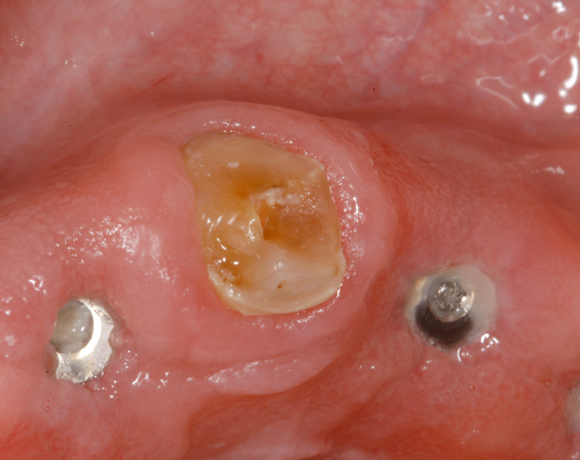

Im nachfolgenden Patientenfall wird ein Zahn mit einem Stift soweit aufgebaut, dass es möglich wird ihn wieder mit einer Krone zu versorgen.